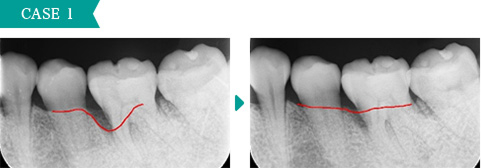

下の前歯の裏側に歯石が大量についていましたが、歯石を除去してブラッシング指導をした後、歯ぐきが改善しました。